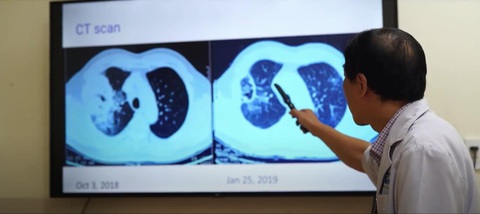

Sau khi làm xét nghiệm và kết quả phù hợp, ông bắt đầu được điều trị bằng liệu pháp miễn dịch. Cứ 3 tuần 1 lần, ông lại đến bệnh viện. Đã 4 năm trôi qua, tiếp xúc rất nhiều bệnh nhân nhưng bác sĩ Nguyễn Tuấn Khôi - người trực tiếp điều trị cho ông vẫn còn nhớ rất rõ: "Ông vào bệnh viện khi ung thư phổi đã vào giai đoạn 4, khối u ở bên phổi phải rất lớn, di căn rất nhiều 2 phổi. Khi nói chuyện với tôi, giọng ông bị đứt quãng vì khó thở. Nhưng sau khi điều trị bằng liệu pháp miễn dịch, thì chỉ sau 1 - 2 chu kỳ đầu tiên, kết quả đã có những chuyển biến thấy rõ. Các triệu chứng như mệt, khó thở đã giảm đi 50%. Sau khi điều trị hơn 2 tháng, chụp CT lại thì kích thước khối u đã giảm rất ngoạn mục".

Kích thước khối u đã giảm đi nhanh chóng chỉ sau hơn 2 tháng điều trị bằng liệu pháp miễn dịch

Hiện nay, cứ 4 - 6 tháng, ông đi tái khám và chụp CT một lần. Khi mới phát hiện, kích thước khối u là 3 con số, nhưng sau một thời gian điều trị, kích thước khối u chỉ còn 2 con số. "Đến lần tái khám vừa rồi, khối u chỉ còn 2 con số. Tôi cũng hy vọng trong quá trình điều trị mà nó cứ nhỏ lần đi thì rất mừng", ông phấn khởi nói.